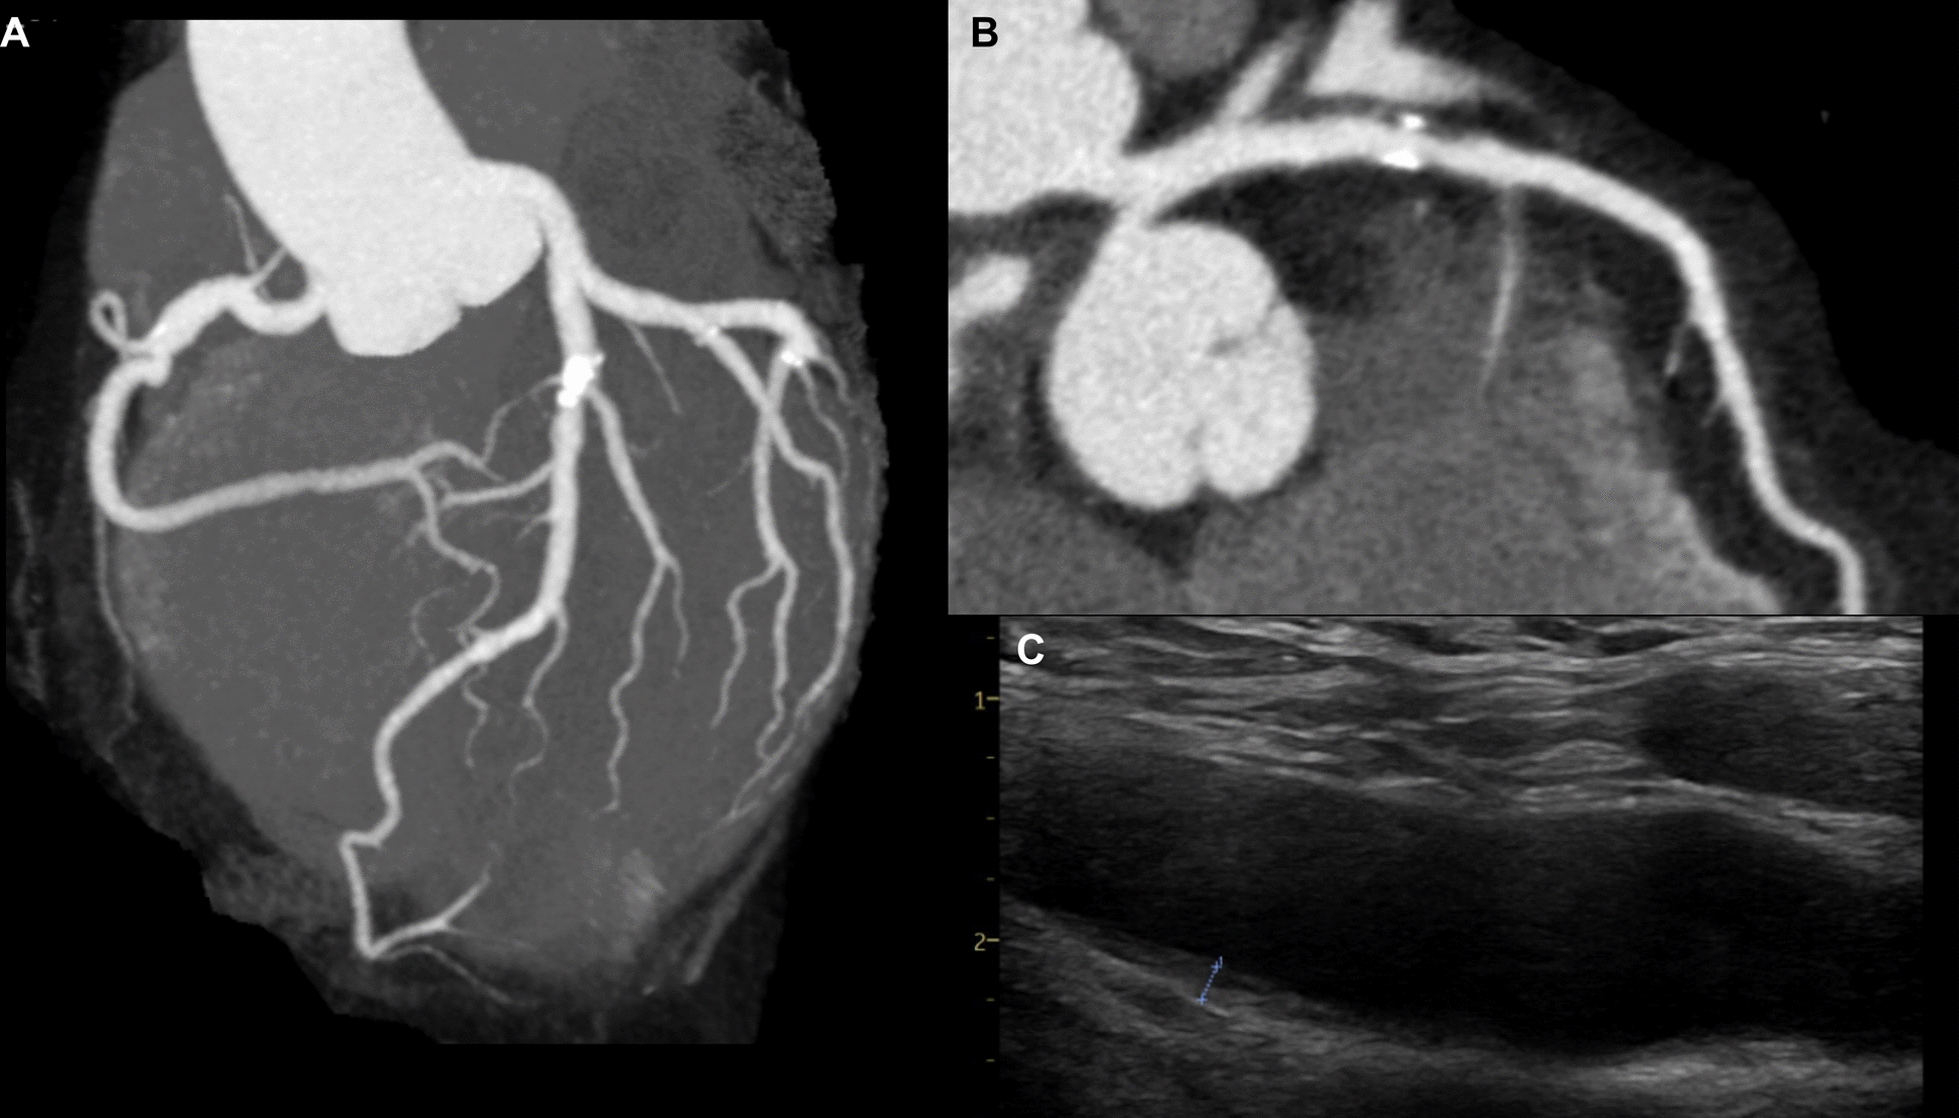

Case presentation: We report a 53-year-old Japanese man who was clinically diagnosed with familial hypercholesterolemia. He presented with marked Achilles tendon xanthomas and refractory hyper-low-density-lipoprotein cholesterolemia. Initiation of intensified lipid-lowering therapy, including inclisiran, resulted in improvement of hyper-low-density-lipoprotein cholesterolemia. Genetic testing revealed heterozygous mutations in CYP27A1 (p.Arg405Gln) and apolipoprotein B (APOB) (p.Pro955Ser). He had no neurological symptoms, cataracts, or other features suggestive of cerebrotendinous xanthomatosis without Achilles tendon xanthomas.

Conclusion: This case highlights a rare presentation of a potential CYP27A1 heterozygous mutation-related phenotype. The APOB (p.Pro955Ser) variant is associated with reduced low-density-lipoprotein receptor activity, contributing to hyper-low-density-lipoprotein cholesterolemia and Achilles tendon xanthomas. However, this patient's Achilles tendon xanthoma was thicker than those reported in previous cases with APOB (p.Pro955Ser) gene mutations, suggesting a potential contribution from the CYP27A1 mutation. Although the patient did not exhibit elevated serum cholestanol levels or other cerebrotendinous xanthomatosis features, the marked Achilles tendon thickening raises the possibility that the combination of a heterozygous CYP27A1 gene mutation and an APOB gene mutation contributed to the condition.